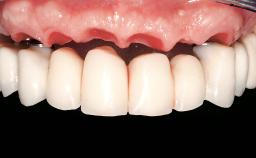

Immediate Loading of Eight Implants in the Maxilla and Six Implants in the Mandible and Final Restoration with Three-Unit and Four-Unit FDPs

Prosthesis Type FDP

SAC Level Complex

Defining Characteristics Fully edentulous upper jaw to be rehabilitated with an implant-borne fixed dental prosthesis

Loading Protocol Immediate

Retention Cemented, with prosthesis margin < 3mm submucosal Cemented, with prosthesis margin < 3mm submucosal

Esthetic Risk High

Provisional Implant-Supported Prosthesis Prosthodontic margin < 3 mm apical to mucosal crest Prosthodontic margin < 3 mm apical to mucosal crest